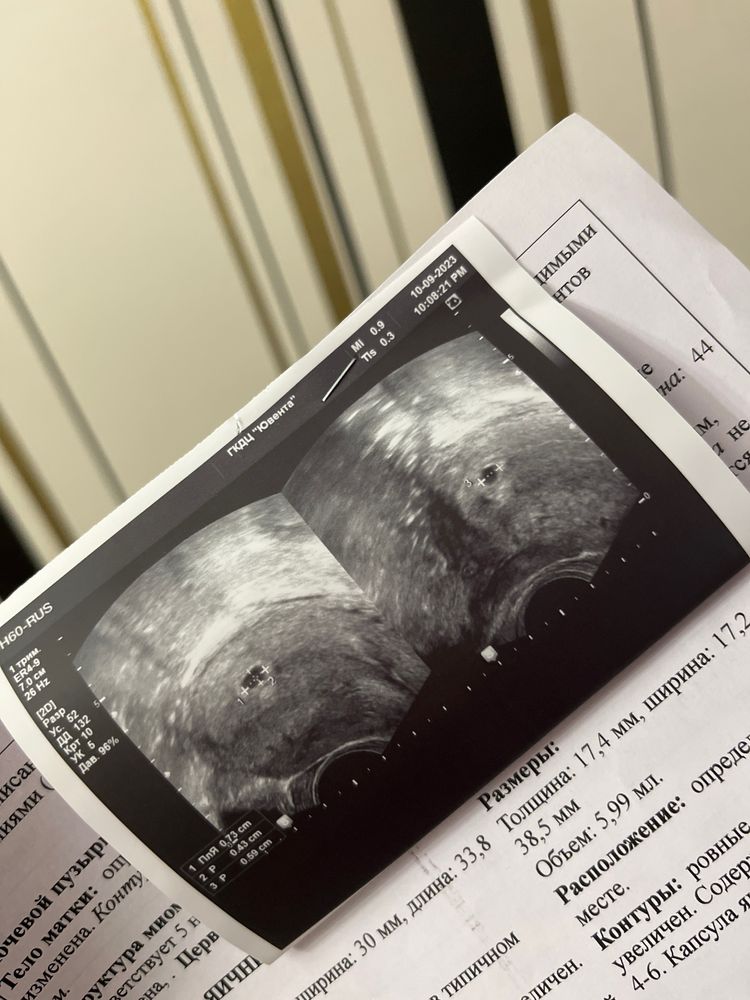

Nadezhda, я ходила на узи, написали, что была овуляция справа